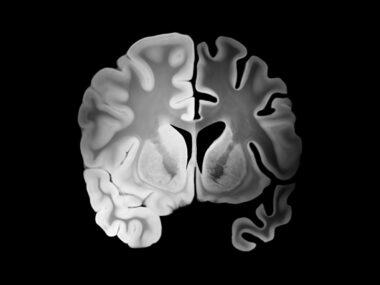

This banner image for Ben Hofmeister's column